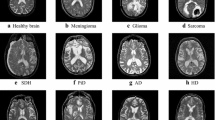

In this paper, a new approach for classification of brain tissues into White Matter, Gray Matter, Cerebral Spinal Fluid, Glial Matter, Connective and MS lesion in multiple sclerosis is introduced. This work considers fuzzy multiwavelets, Gaussian Mixture Model (GMM) and Weighted Probabilistic Neural Networks (WPNN) for the classification of the brain tissues. Multiwavelet packet transformation is employed on brain MR images. Since multiwavelet packet transformation yields larger number of subbands compared to multiwavelet and wavelet transformations, we have proposed a fuzzy-set based theory for selection of the subbands. In contrast to the standard method of subband selection, guided by the criteria of signal energy, our method is based on the discriminatory features from the multiwavelet packet transformation coefficients. Singular values are then computed from the selected subbands. The singular values of lower magnitudes are truncated for effective classification of brain tissues in the presence of noise. Probability density functions of the remaining singular values are modeled as GMM. Model parameters are estimated using stochastic EM (SEM). They are used as features for the classification. The classification is carried out using WPNN. Experiments have been carried out using the data sets composed of three modalities of brain MR images, namely T1 and T2 relaxation times and proton density weighted MR images. Experimental results prove that the proposed approach gives better classification rate at various noise levels compared to existing approaches.